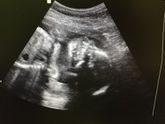

Узи

10 мая 2017 17:38

Сходила сегодня на плановые узи☺️ все у нас хорошо, срок по месячным 24,5, по УЗИ ставят также. Вести мы уже 728 грамм, даже не верится☺️ доча перевернулась и теперь в головном предлежании и плацента радует, поднялась на 1 см и теперь выше внутреннего … Читать далее